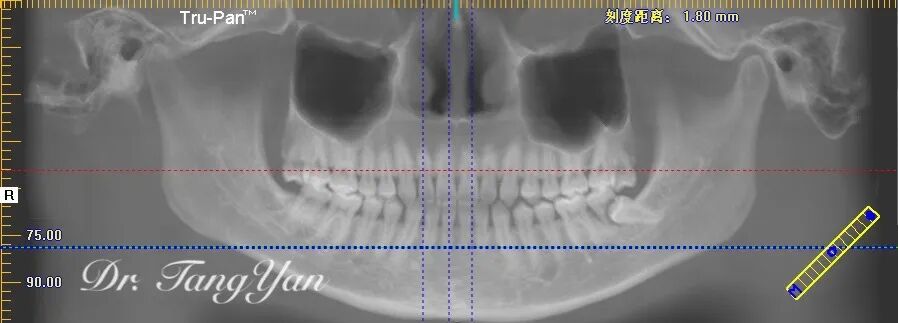

下面这张图,小7牙根的位置被小8的头部占据,小7都快没有生存之地了!